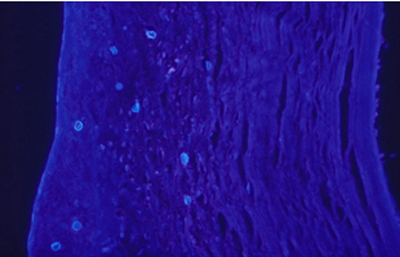

Las imágenes de Acanthamoebas muestran una cápsula circular u ondulada, refringente de color azulado o verde manzana, notablemente más intensa que los materiales y tejidos que la rodean. Suelen medir de 12 a 16 µm de diámetro. El contenido del quiste es azul tenue. (Figura 37 , 38, 39 y 40)

Fig. 37 Blanco de Calcofluor (CW). Original x160

Fig. 38 CW, Original x250

Fig. 39 CW, Original x160

Fig. 40 CW, Original x160